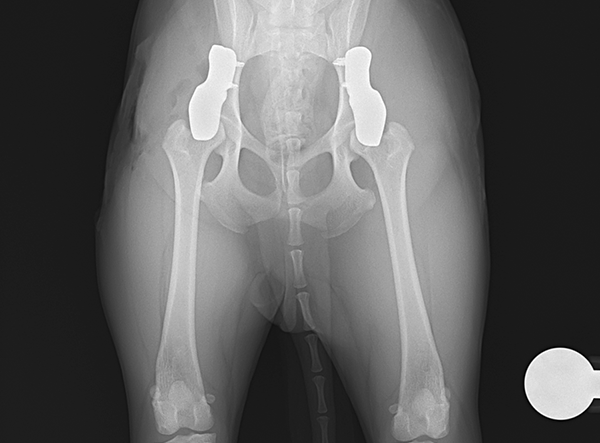

In July 2025, a tiny Shiba Inu weighing only 5.8 kg underwent a pioneering procedure for bilateral hip dysplasia — becoming one of the smallest dogs ever to receive a 3D HIP Implant Implant by Rita Leibinger.

The surgery involved implanting a 2.4 mm 3D HIP Patient-Specific Implant (Titanium) to address severe bilateral hip dysplasia. According to Prof. Dr. Björn Meij (Utrecht University), this miniature Shiba Inu represents the smallest patient on Earth to have successfully undergone this advanced orthopedic procedure. The precision and adaptability of the 3D HIP system allowed for a stable and minimally invasive intervention, tailored to the patient’s unique anatomy.

Post-operatively, the Shiba Inu is progressing well, showing encouraging signs of improved joint stability and mobility. While full rehabilitation will require time and care, the early results are highly promising, resulting in greatly reduced pain and enhanced mobility.

Implant Used: 2.4 mm 3D HIP Patient-Specific Implant – Titanium